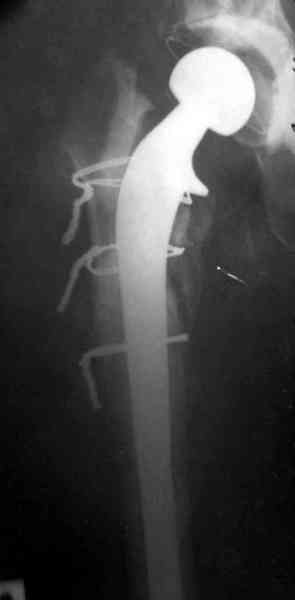

Представляю вашему вниманию снимки (прошу прошения за качество снимков) больной 48 лет с ревматоидным артритом, которой был сделан тотальный эндопротез справа,

контрольный снимок сделали только на 21день после операции (№1) и с интервалом 5 дней второй снимок (№2)

Судя по всему, произошел раскол наружной стенки бедра и ножка находится вне костного канала. В таком случае

решение одно - удаление ножки и установка новой в расчете на дистальную фиксацию. Конктреную модель подсказать тяжело из-за низкого качества Р-грамм.